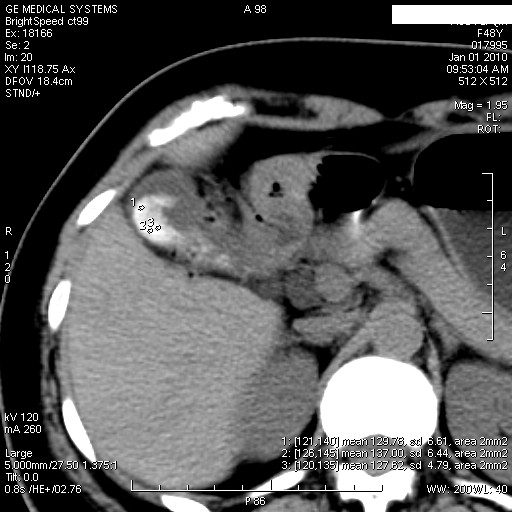

1.图像看上去不是同一人(前组图像十二指肠未见明显异常,后组图像可见十二指肠占位)

2.后组图象印像

a.十二指肠球部前壁占位

b.坏蛆性胆囊炎,胆囊-结肠瘘(瘘口微小且时间较短,结肠内容返流入胆囊,形成胆囊壁钙化,胆囊内钙盐等沉积)

c.胆管炎,肝外胆管轻度扩张